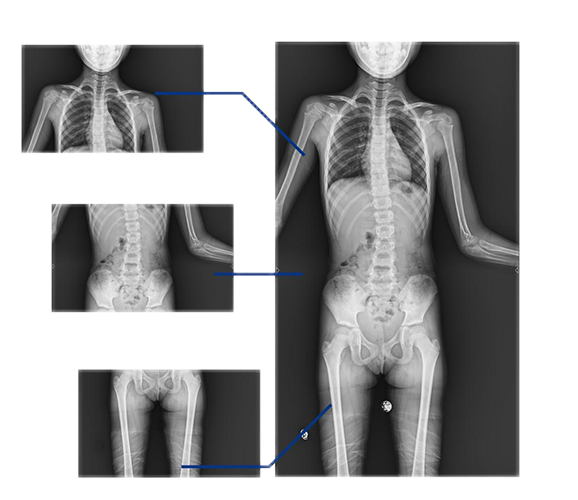

同時(shí),動(dòng)態(tài)DRF的全景拼接技術(shù)能夠輔助脊柱畸形矯形治療、康復(fù)檢查,為臨床提供高精度圖像。該技術(shù)可自動(dòng)或手動(dòng)拼接,圖像無(wú)拼接痕跡,全脊柱重組影像準(zhǔn)確率高、結(jié)構(gòu)清晰。在脊柱側(cè)彎患者的康復(fù)治療中,拼接技術(shù)的應(yīng)用還有助于臨床對(duì)患者的脊柱整體形態(tài)、病變程度等進(jìn)行全面而直觀地掌握,為后續(xù)的治療提供良好的支持。